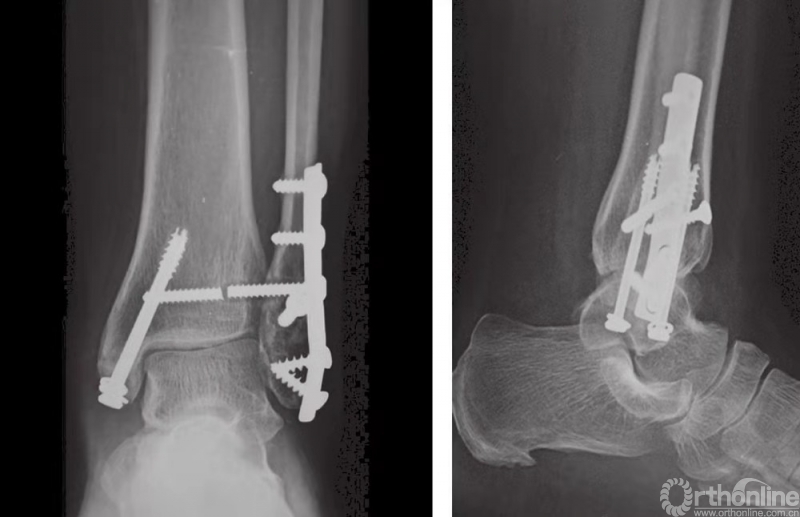

下胫腓联合固定技术

在完成所有踝部骨折的固定之后,应评估下胫腓联合的稳定性。如果下胫腓联合关节上方或下胫腓联合水平发生腓骨骨折,应充分检查下胫腓联合的稳定性。在前后和中外两个平面上,应检查其完整性(图23)。另外,因为下胫腓联合发生损伤时腓骨可能向外旋转,故还应检查腓骨的旋转情况。

如果下胫腓联合不稳,则须进行固定,固定时采用皮质骨螺钉。由于腓骨在解剖关系上位于胫骨的后外侧,因此应将螺钉从后向前以30°的角度嵌入。一般认为,三皮质骨螺钉固定足以保证下胫腓联合的稳定性。螺钉应至少高过关节线2cm(图24和图25)。